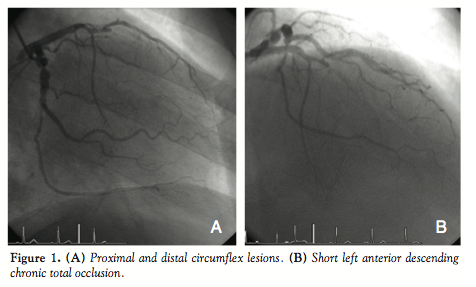

Case Report. A 58-year-old gardener with a past history of smoking, hypertension, and hyperlipidemia was admitted with chest pain, anterolateral ST depression, and a small troponin leak. Coronary angiography was performed through a 5 Fr right radial approach and

showed 90% stenosis in the proximal circumflex artery, 80% stenosis in the distal circumflex, and 100% short-segment CTO in the mid-left anterior descending (LAD) artery (Figure 1). Although the CTO was calcified, it was deemed to be short and therefore a slender PCI approach was taken.